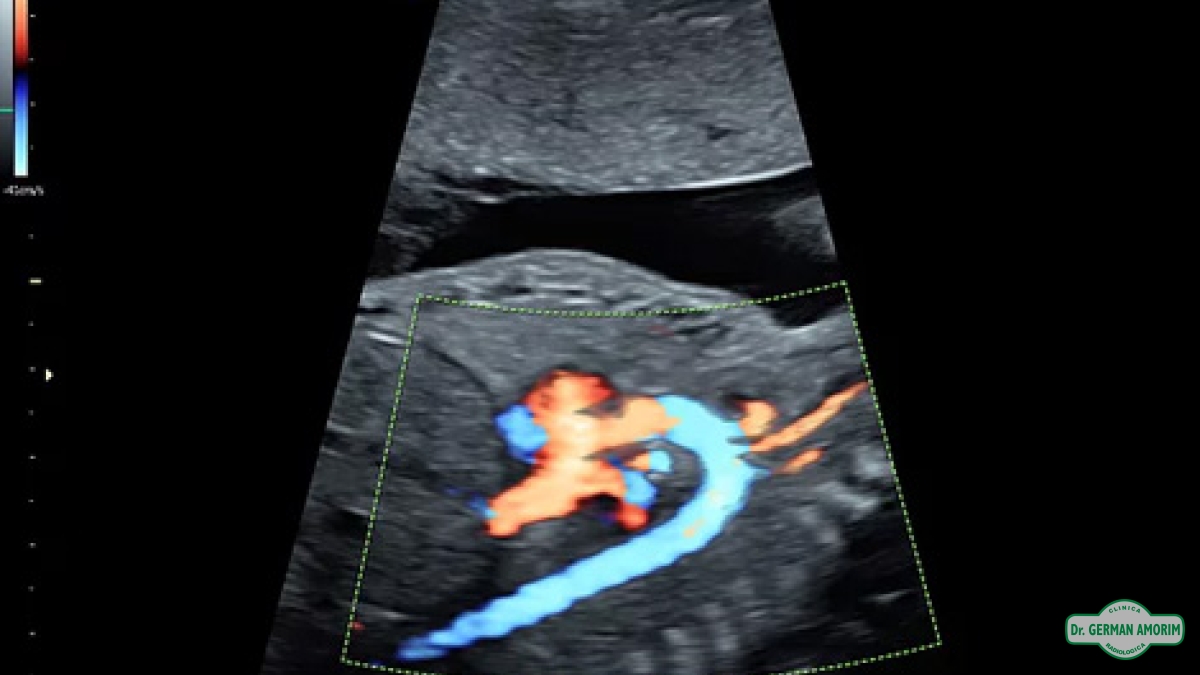

Equipo de Alta Gama Multiproposito para todo tipo de estudios, calidad de imagen superior para el diagnóstico preciso, 4D/5D con HD Live para imágenes del feto únicas color natural, Doppler de.

Alta resolución HD Flow para detectar vascularizacion donde el Doppler común no detecta flujo

• Visualización vibrante de la anatomía y la función con Doppler color avanzado